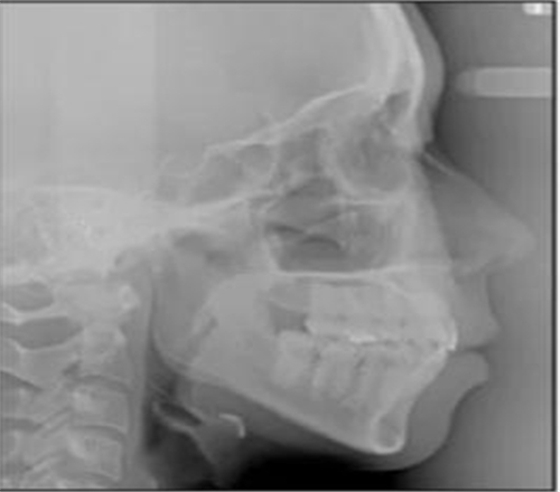

頭側(cè)分析提示為骨性安氏II類(ANB,8.4°;Wits,3.6mm),高角(SN-MP,44.9°),上頜切牙略舌傾(U1-SN,96.2°),下頜切牙略舌傾(IMPA,88。3°)(圖2;表)

治療后頭側(cè)數(shù)據(jù)提示:無(wú)明顯骨性變化(上頜SNA82.1°,下頜SNB74.9°),上頜前牙得到內(nèi)收,略舌傾,頦部前后位置無(wú)明顯改變,仍未凸面型(圖8,表)。將治療前后圖像重疊后結(jié)果如(圖8及圖9),24月后隨訪結(jié)果見(jiàn)圖10.